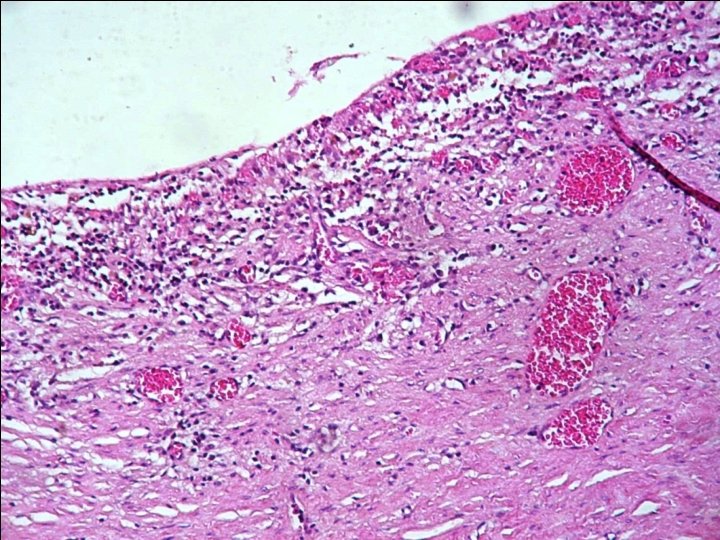

Pathology § Microscopic Description: Sections show fibrotic cyst wall with columnar epithelial lining, inflammation and ulceration area. § Diagnosis: Choledocal cyst wall, resection: - Cyst wall with fibrosis, hemorrhage, acute & chronic inflammation and ulceration.

§ Pathologic features of choledochal cysts are variable, ranging from normal bile duct mucosa to carcinoma. § More commonly in children there is a densely fibrotic cyst wall with evidence of chronic and acute inflammation. § In adults, there are frequently inflammatory changes, erosions, sparse distribution of mucin glands, and not infrequently metaplasia.